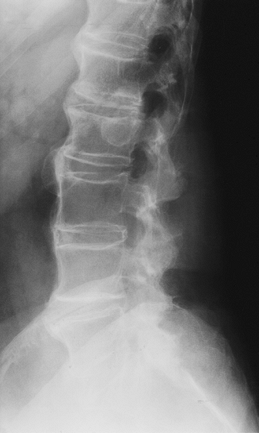

FIGURE 3-66 Spinal chordoma. (A)

Lateral radiograph shows sclerosis and compression of L1 (15% of chordomas involve the spine, 50% involve the sacrum, 30% to 70% may calcify). Sagittal T1-weighted (B) and T2-weighted (C) and axial contrast-enhanced image (D) demonstrate extension of tumor from L1 to L2 with extension around the dural sac. |